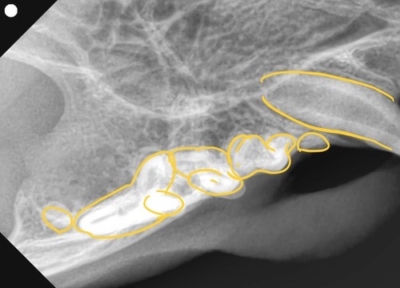

左下顎は正常な数と歯並び

左下顎は中央に重なって生えている過剰歯があります。レントゲンで確認しても、乳歯ではなく永久歯と考えられました。これらは過剰歯と呼ばれ、通常より本数が多く歯が生えてきます。かみ合わせが悪くなり、また歯間が狭くなり歯垢がつき、歯周病になりやすいです。そのため、不必要と思われる歯を抜歯しました。また、歯肉の増殖している部分を一部切り取り病理検査用の検体とし、それ以外の部分はメスで切除し正常に近い歯肉の形状に近づけました。